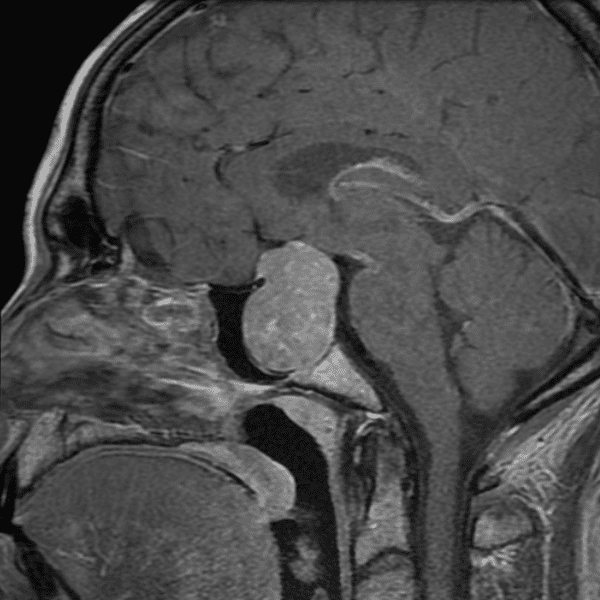

Classic Cases